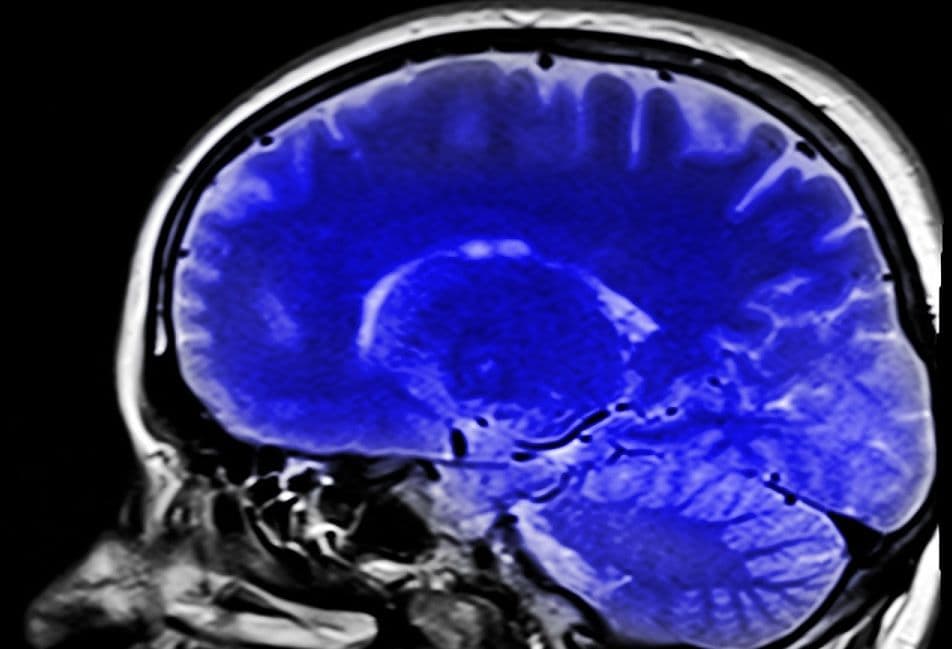

Mr Brain brengt hersenen beter in beeld

In het project ‘MR Brain’ wordt gewerkt aan een snellere en kwalitatief hoogwaardige MRI van de hersenen. Bij de huidige technologie worden neurologisch onderzoek en diagnose belemmerd door lage beeldresolutie en lange scantijden. In het project wordt een serie high-tech producten samengebracht tot één hard- en software product (plug ’n play). Het consortium Stichting Katholieke Universiteit- RU (Nijmegen), MR Coils B.V. (Zaltbommel), Screenpoint Medical B.V. (Nijmegen) en Stichting Katholieke Universiteit- Radboudumc (Nijmegen) ontvangt hiervoor een totaal subsidiebedrag van € 1.980.482 de totale kosten bedragen € 4.951.204.